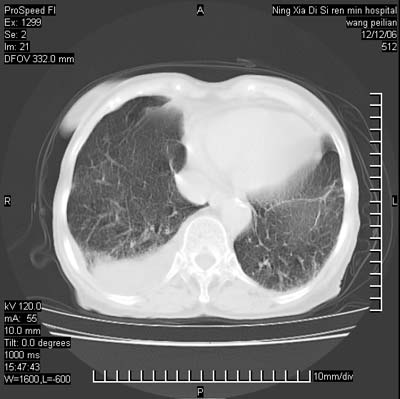

两肺可见多个大小不等的结节,左侧有胸水,纵隔淋巴结增大,考虑是细支气管肺泡癌

两肺尖纤维索状影,两下肺结节块状影,且有钙化灶,右胸腔积液。考虑肺结核并胸膜炎。

双侧肺结核伴右侧胸腔积液.

两肺尖纤维索状影,两下肺结节块状影,且有钙化灶,右胸腔积液。考虑肺结核并胸膜炎肺间质纤维化

两肺以间质性病变为主,并有胸腔积液,考虑结核

考虑:1、慢性支气管炎合并全小叶型肺气肿、间质纤维化;

2、双肺结核;

3、右侧胸膜炎(积液)。

1、双肺继发型肺结核(以纤维、增殖灶为主);

2、右侧胸腔积液;

3、其余符合老年肺改变。

双肺见多个结节状及条索状影,双侧胸腔积液,右侧叶间积液,考虑结核性胸膜炎